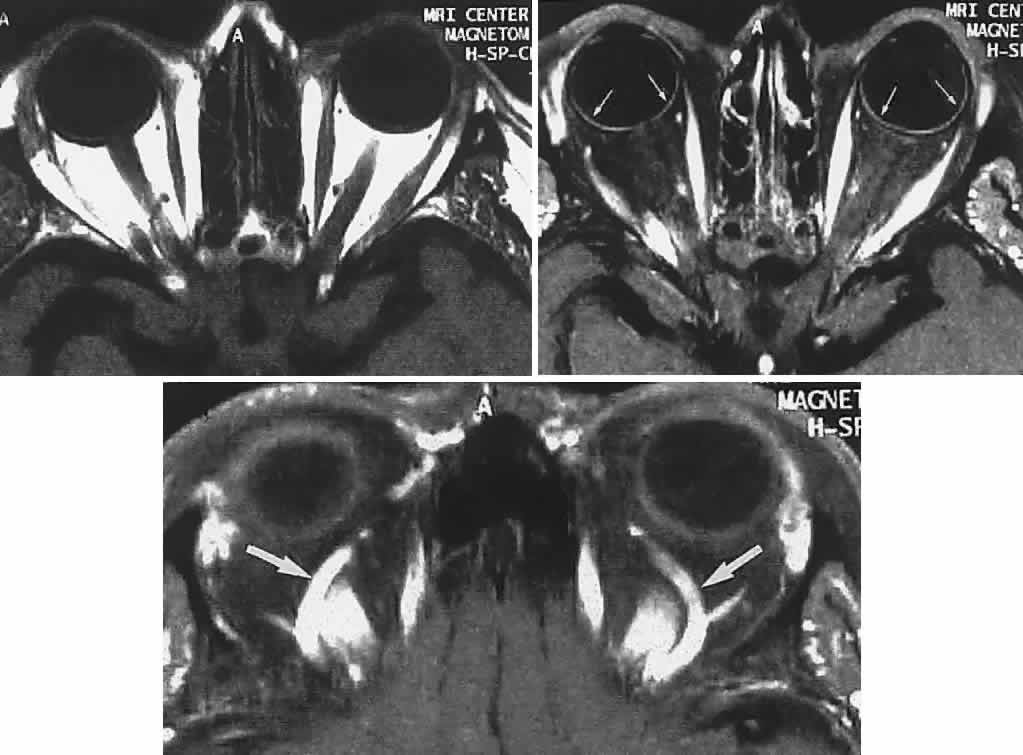

Now almost universally available, MRI is the preferable technique for imaging the soft tissue contents of the orbit, high-resolution 3-mm and thinner sections being available, as well as gadolinium contrast enhancement (Figs. 19, 20, and 21).

Fig. 21. Young patient had slowly evolving unilateral proptosis. Left. Enhanced CT scan shows laterally placed homogeneous mass. Right. MRI with contact coil shows mass well separated from optic nerve and splaying lateral rectus (arrows) on medial surface of lesion; tumor was a fibrous histiocytoma.